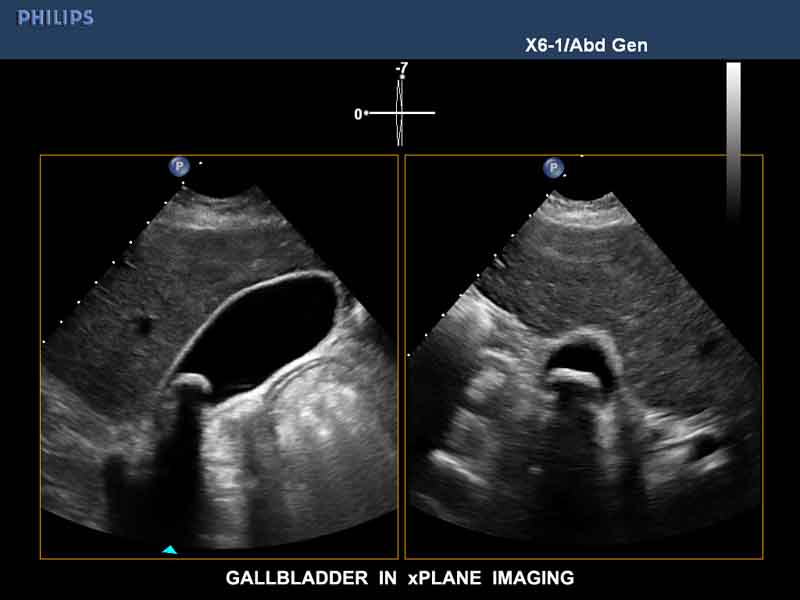

xMatrix zondes elementu izkārtojums matricā sniedz iespēju attēlot divās savstarpēji perpendikulārās plaknēs – Live xPlane programma. Šodienas ultrasonogrāfijā ar Live xPlane funkciju iespējams izmeklēt jebkuru iekšējo orgānu garenvirziena un šķērsvirziena plaknēs vienlaicīgi. Live xPlane funkcija darbojas arī ar Color Doppler režīmu.